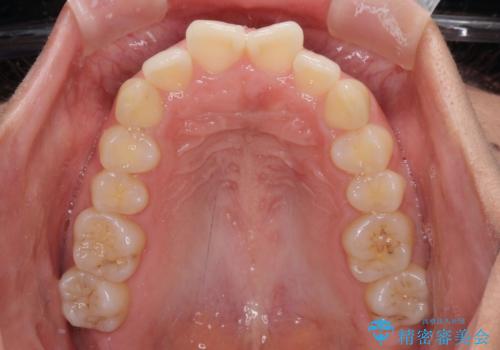

- 前歯の出っ歯と口元の閉じにくさを気にして来院された患者様です。

口元を積極的に引っ込めるために、上下左右の小臼歯4本を抜歯することとしました。

4本の歯を抜歯したことで、飛び出していた口元が引っ込み、横顔が大きく改善されました。

咬み合わせが悪化することのないようにスペースを閉じていくことができ、比較的スムーズに治療を進めることができました。